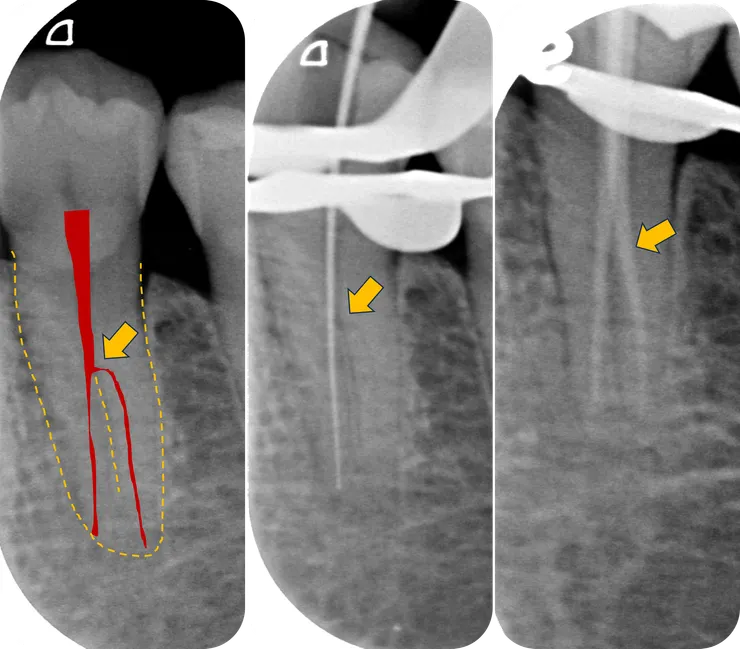

面對這樣接近直角的入口彎度,必須把對付 [ curved canal ] 的技巧拿來運用:

1. 如同移除 cervical shelf 般,先移除入口外側蓋過來的 dentin.

這個 case 我使用的是土法煉鋼的 #10 - #35 K file 來完成這個任務。可以看到與上頁圖相較之下,蓋在 h 形分岔上方的 dentin 已經被移除了,原本的直角形入口此時已平緩許多。

2. 增加 file 的自由度。

為了拍照,圖中那支 file 被我往 lingual 推。

由於分出來的 canal 在 DL side, 可以想像進去 DL 方向的 file handle 原本是倒向 MB 而被 access cavity 的 MB side 卡住的,所以只要用 high speed bur 把卡住 file 的那區齒質修掉一些,就可以增加 file 的自由度了。

這是修形完成後的樣子。

橘色箭頭指的是修掉 h 形分岔入彎處外側上方齒質後的樣子。

黃色箭頭指的是修掉卡住 file 的冠部齒質後的樣子。

修掉這兩處齒質後,NiTi rotary file 才得以順利地進入 lingual canal 修形,最後兩個 canal 都擴大到 PTG F1.

RCF 時一樣先 fil 困難的 lingual canal, 燙到分岔處後,再 fil buccal canal.

如右邊 X 光片所示,這顆的 common canal 擴得夠大可以同時放進兩支 PTG F1 GP.

對照之下可以看得出來橘色箭頭所指的那個 h 形直角分岔處被整個修平了。

順利地 RCF.